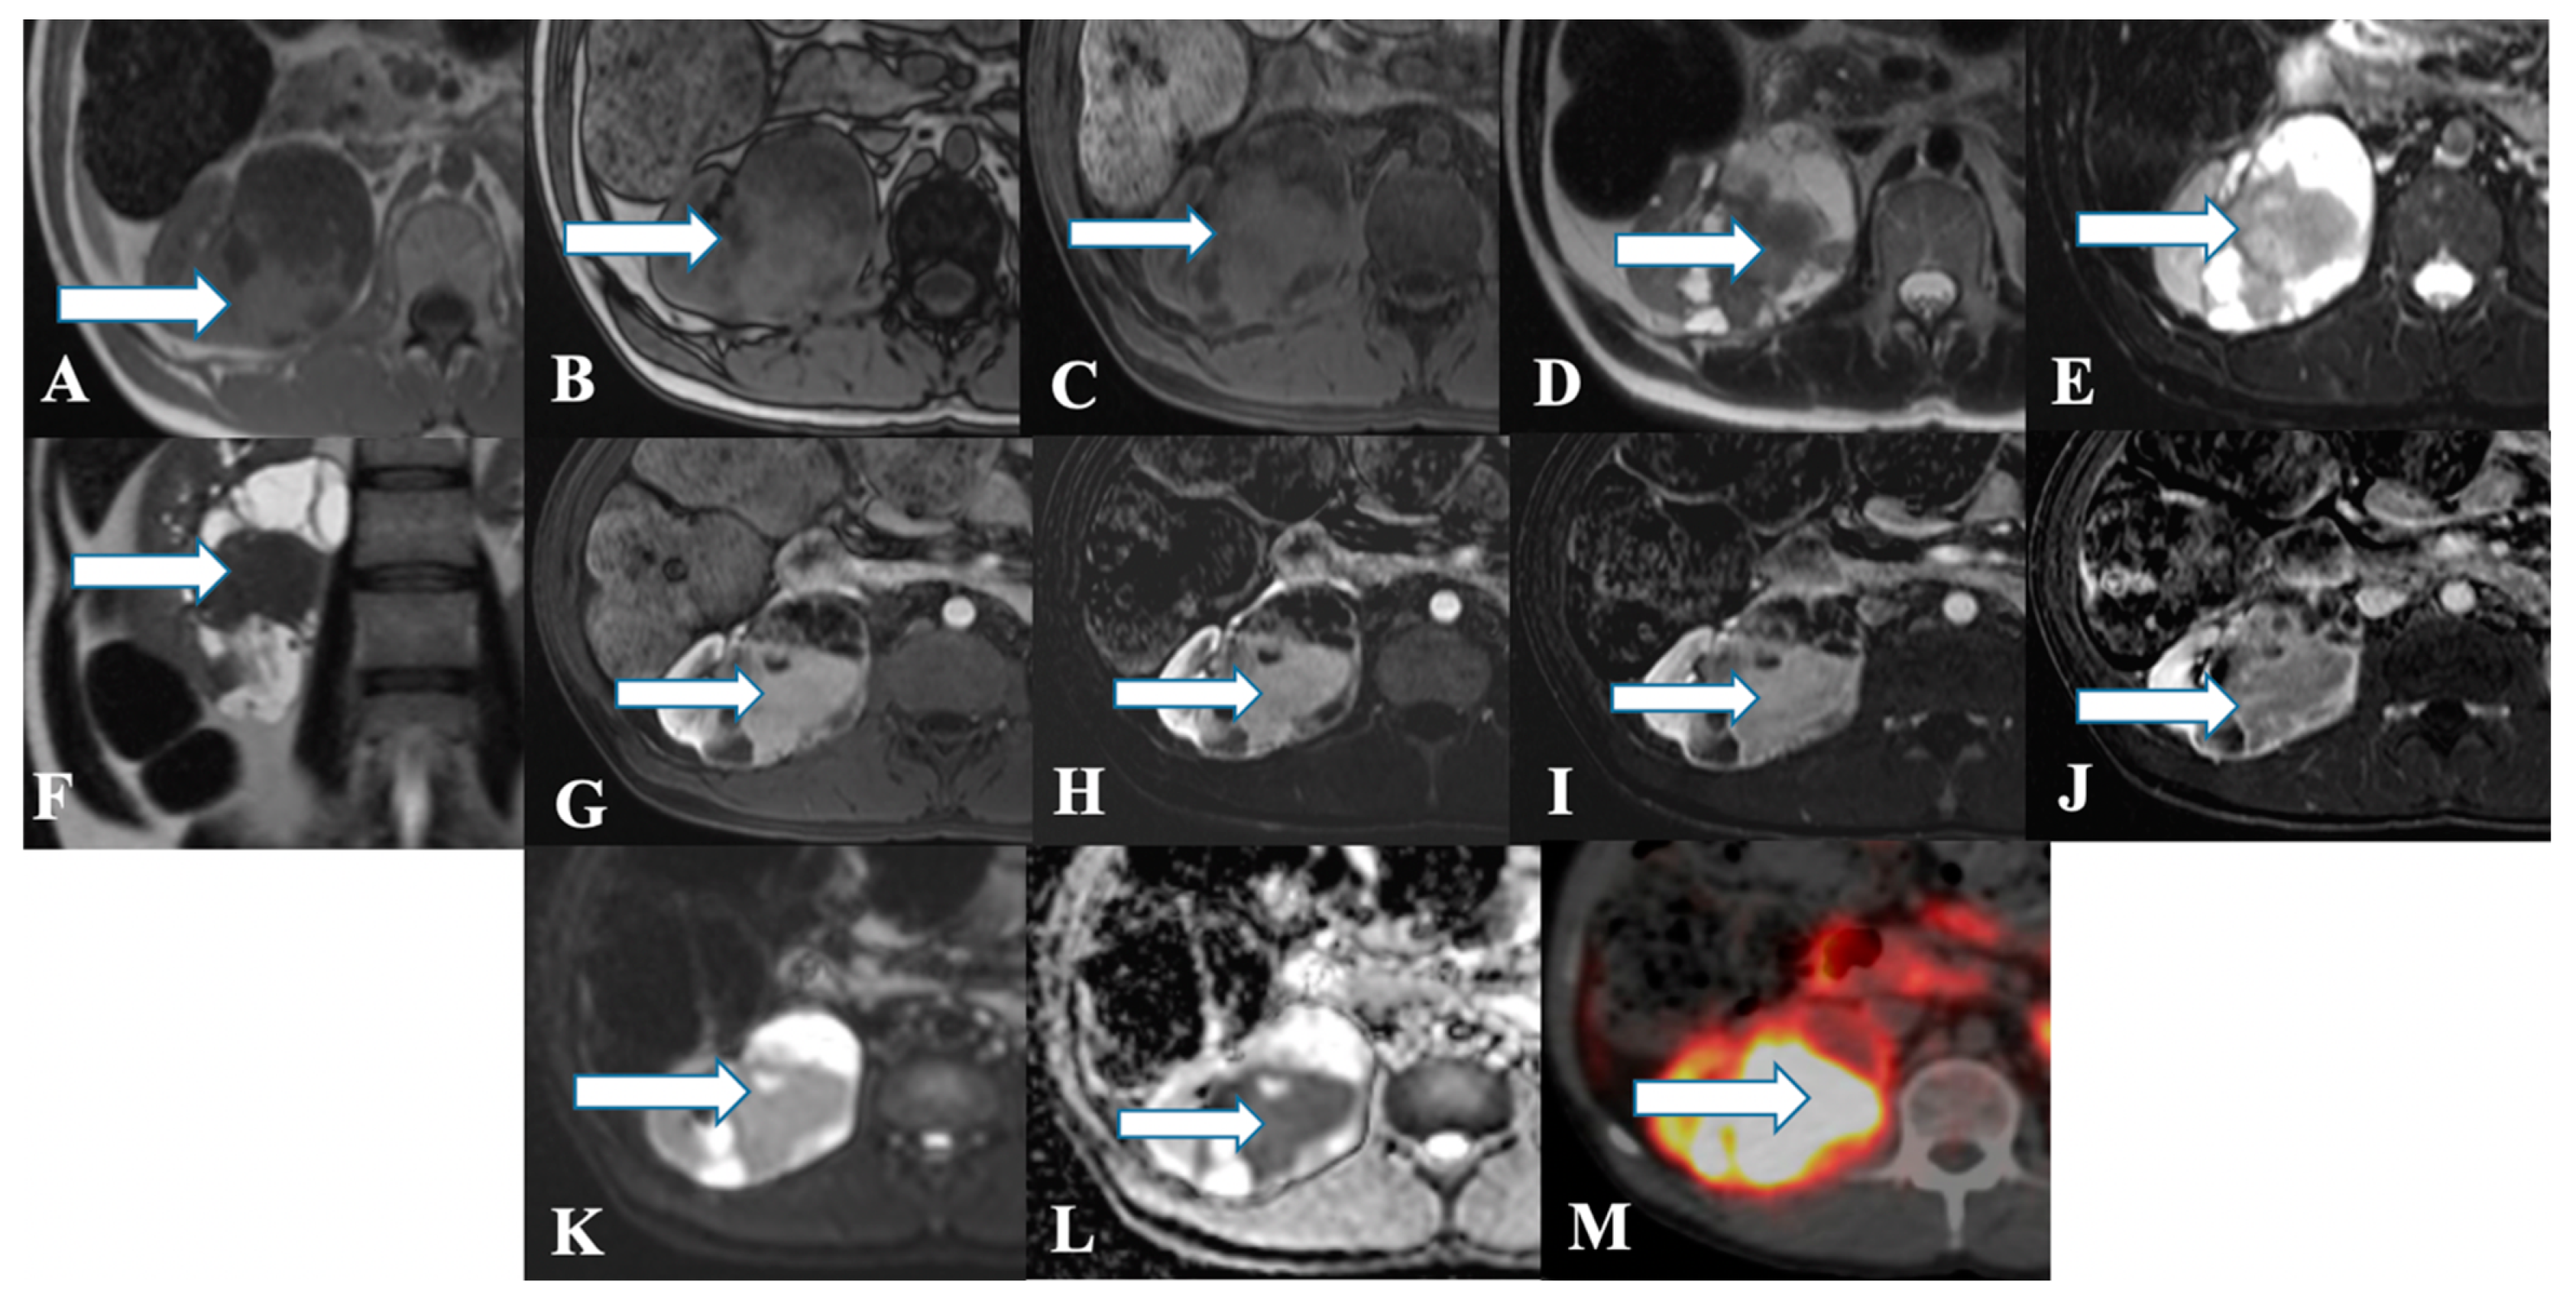

2.3. Imaging

| Renal NET | Heterogeneous solid tumor with cystic component as well; Minimal enhancement on contrast administration; Octreotide scintigraphy: High affinity for somatostatin in 87% of patients. | Heterogeneous signal intensity on T1 and T2WI with areas of high signal intensity on T1WI due to hemorrhage; The mass enhances with contrast administration |